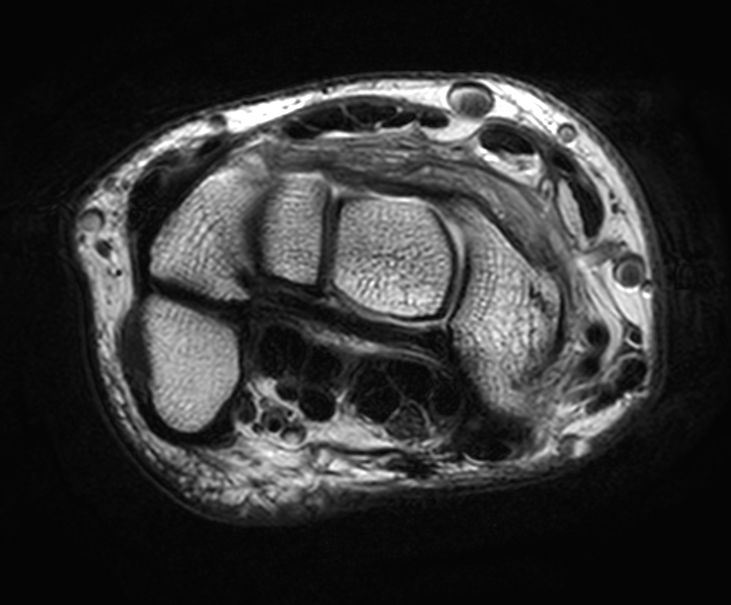

Axial T2w TSE

Axial T2w TSESmartSpeed

Axial T2w TSESmartSpeed Resolution